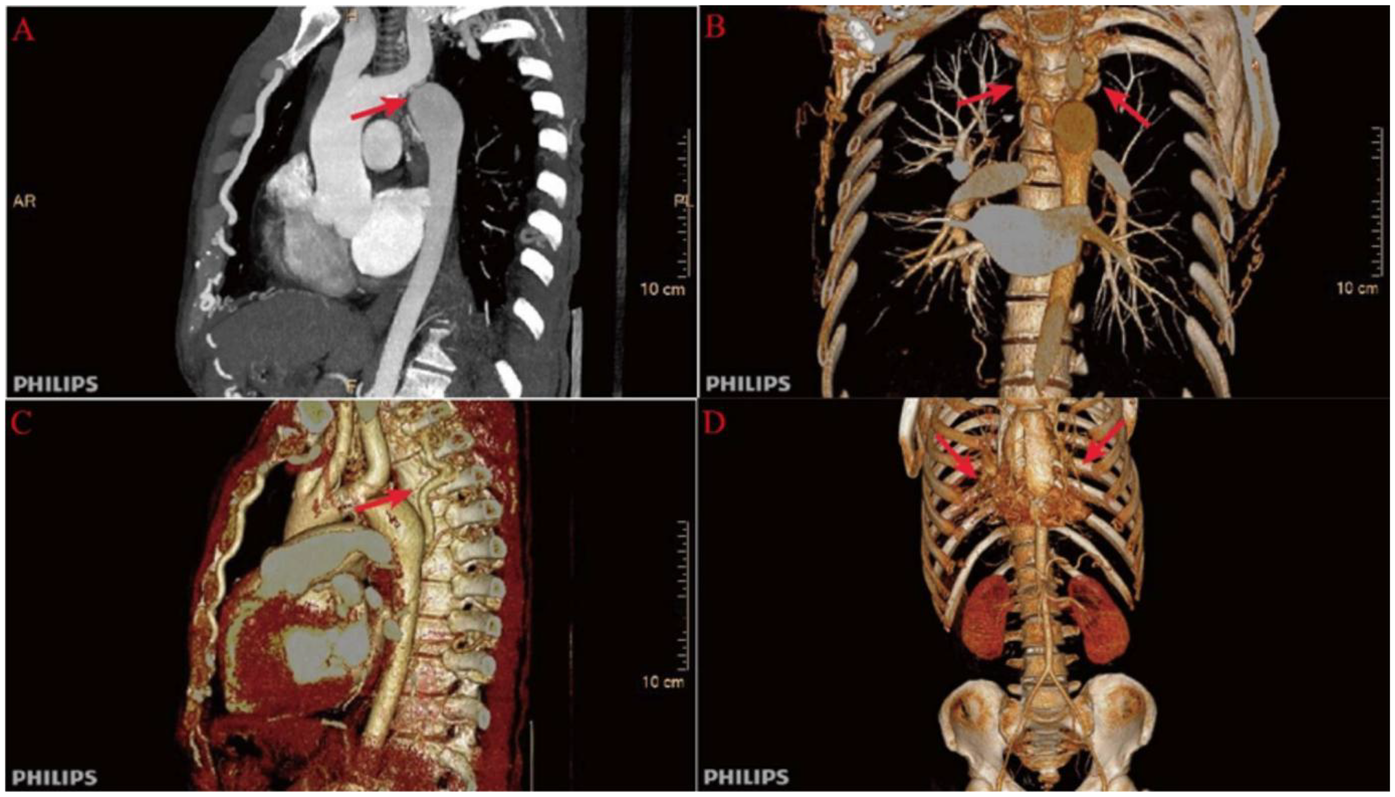

Further evaluation using computed tomography angiography (CTA) confirmed severe CoA, with near-complete interruption of the descending aorta at the isthmus and extensive collateral circulation, including prominently dilated and tortuous internal thoracic arteries (Figure 1). The renal arteries were assessed and found to be unremarkable, with preserved renal function throughout hospitalization.

Figure 1

Preoperative computed tomography angiography (CTA) findings. (A) Severe narrowing at the aortic isthmus (“sandglass-shaped” coarctation, arrow); (B, C) Markedly dilated and tortuous paravertebral arteries, demonstrating extensive collateral circulation; (D) Prominent internal thoracic arteries serving as major collateral pathways.